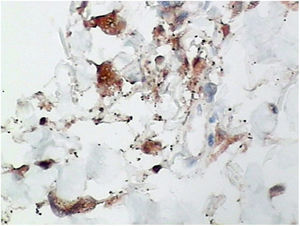

Punch biopsies of the skin lesions were performed, which showed a normal epidermis and fibrohistiocytic proliferation with small vessels in the reticular dermis, displaying lumen vessels filled with prominent endothelial cells, involved with a perivascular inflammatory response composed by multinucleated histiocytic cells (MCs) and a few plasma cells. In the papillary dermis, fibroblastic proliferation and thickened collagen fibers were found (Figs. 2 and 3) and numerous bizarre MCs with scalloped margins were found in the adjacent dermis. The immunohistochemical (IHC) panel performed found the following: S-100 protein (negative), FXIIIa (positive) in MCs, CD68 (positive) in MCs, CD34 and CD31 (positive) in small vessels, and CD4 (positive) in dermal lymphocytes (Figs. 4 and 5). The final diagnosis was established as compatible with multinucleate cell angiohistiocytoma. Due to the benign nature of the illness, the patient chose not to undergo treatment.

In most reported cases of MCAH, the IHC panel performed included staining for factor VIII, factor XIIIa, CD31, CD34, CD68, and vimentin in both the vascular endothelium and MCs. In Frew's review article, IHC showed 60% CD68-stained vascular endothelial cells.10 As expected, endothelial cells also expressed factor VIII staining, CD31, and CD34, and in the present case, CD31 and CD34 markers were also positive in these cells. Frew noted that MCs were negative in staining for endothelial markers, factor VIII, and CD34, with approximately half of the cases positively staining macrophages/histiocytes with factor XIIIa and CD68.10 Factor XIIIa and CD68 were also noted in the MCs of the present case.